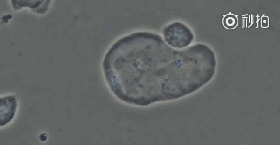

1、NK细胞先头部队进场,尝试性攻击癌细胞。

图片

2、队伍中的一名勇士找到了突破口,癌细胞瞬间瓦解,兄弟部队群起而攻之。